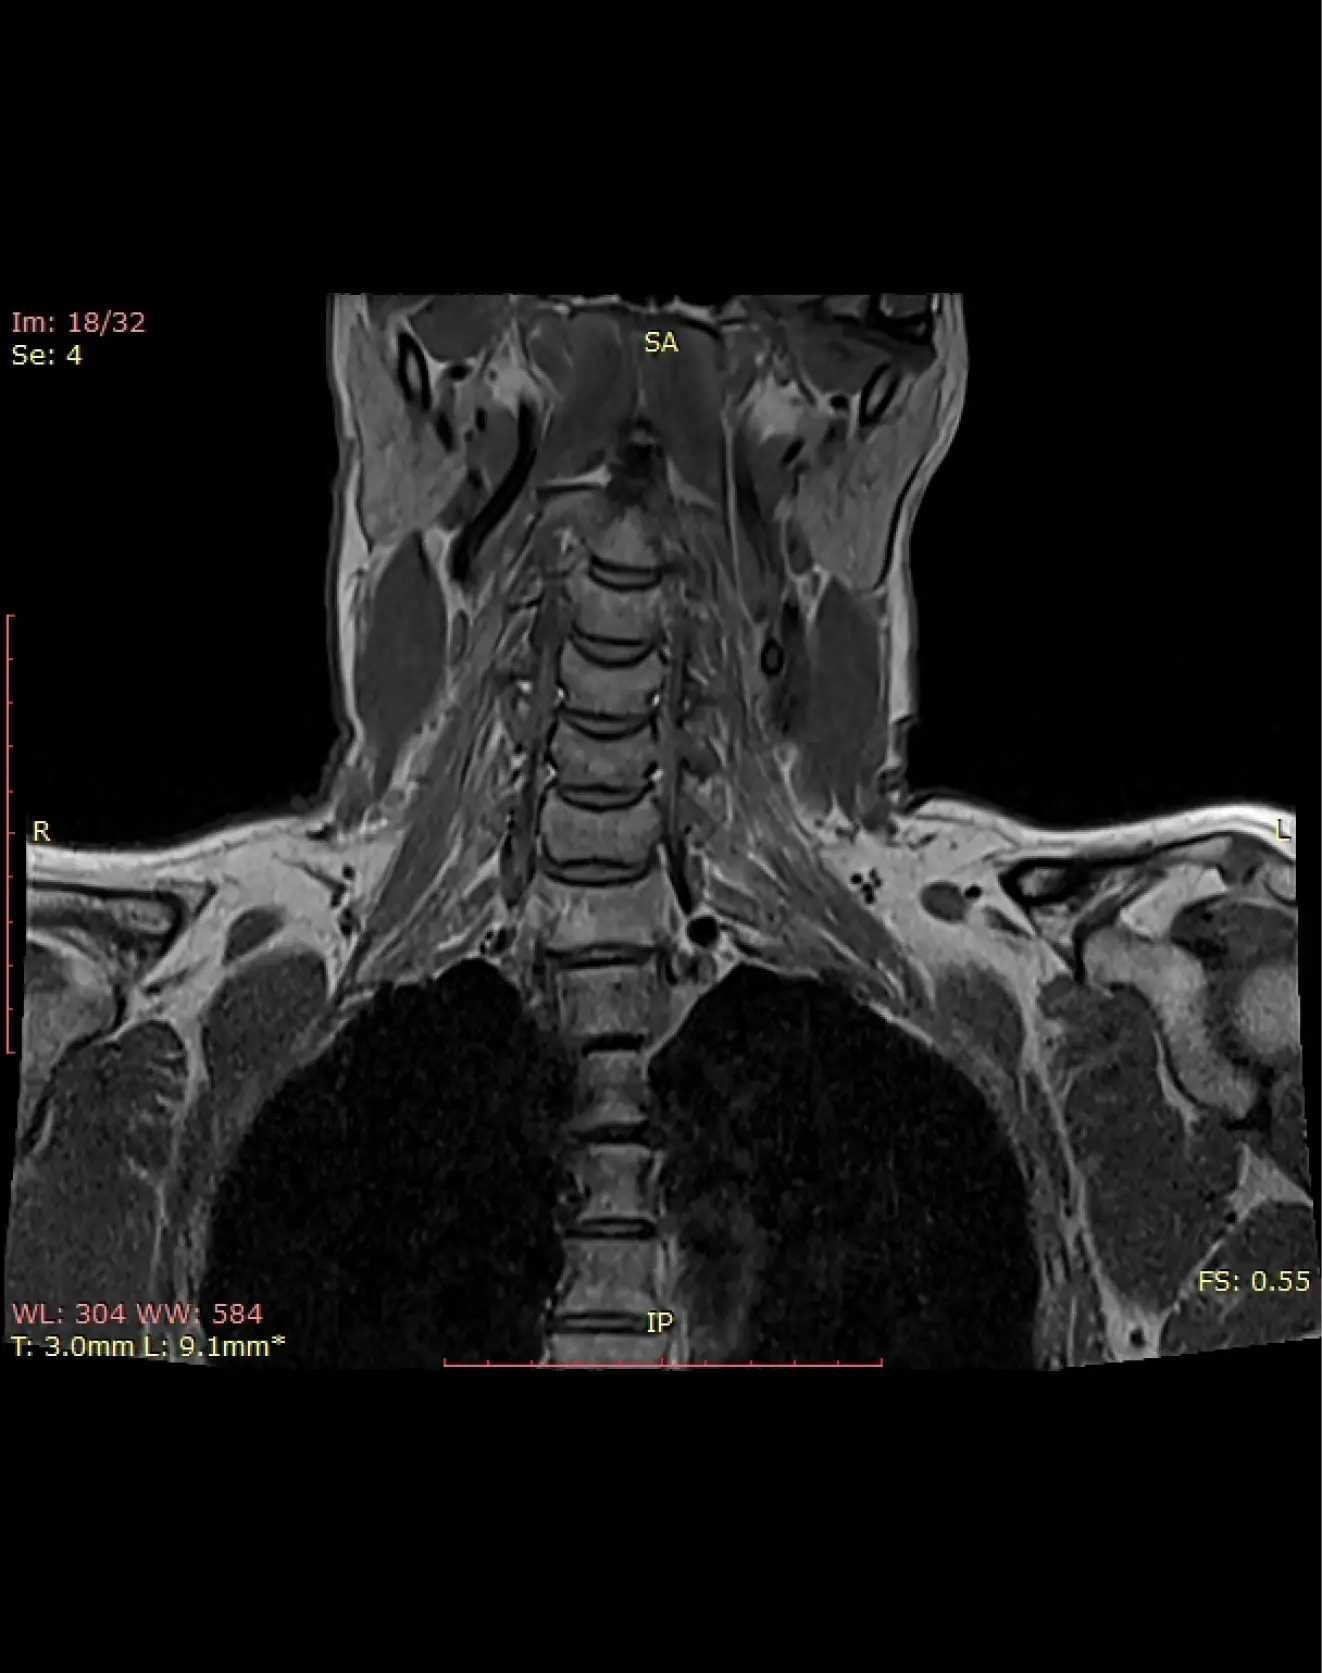

Визуализация позвонков, межпозвонковых дисков, атланто-окципитального сочленения, зубовидного отростка, хода позвоночных артерий, спинного мозга, спинномозговых корешков, окружающих мягких тканей.

Показания:

— Боли в шее

— Обменно-дистрофические изменения (остеохондроз и т.д.)

— Протрузии, грыжи дисков

— Головокружения, шум в ушах

— Радикулопатия

— Ограничение подвижности шеи

— Травмы шейного отдела позвоночника